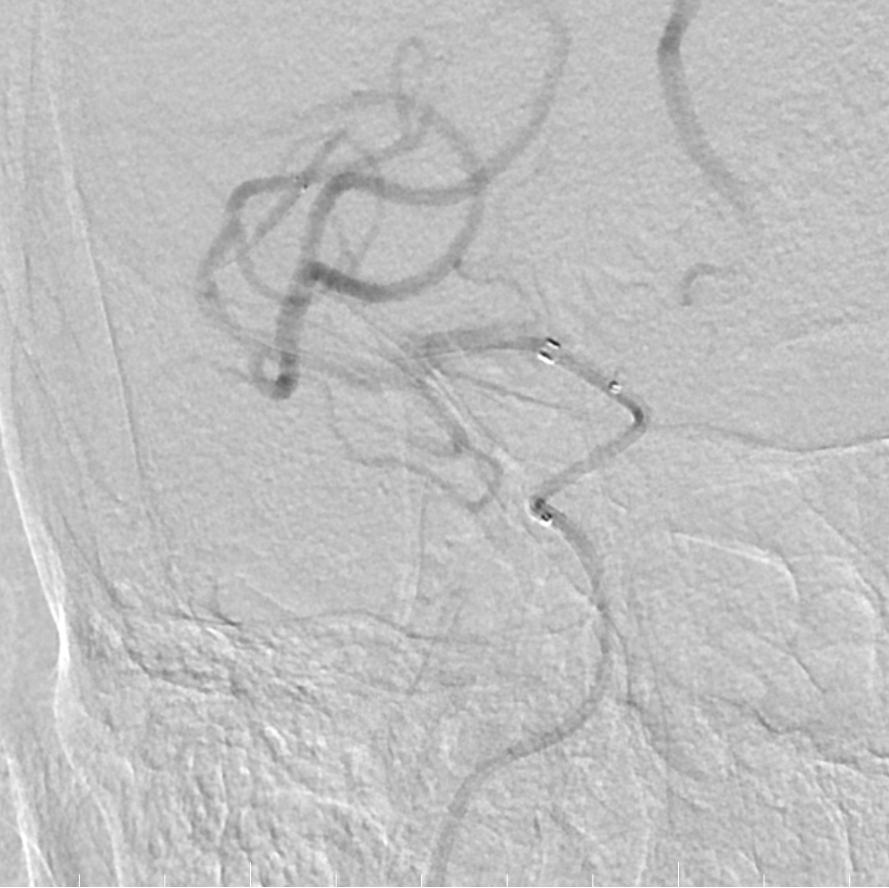

造影提示右侧大脑中动脉M2段下干闭塞。

动脉长鞘怎么置入有励可说|Locaste 088励楷长鞘及Tarvos微导丝在右侧大脑中动脉M2段取栓术中的应用_https://www.jmylbn.com_新闻资讯_第10张

动脉长鞘怎么置入有励可说|Locaste 088励楷长鞘及Tarvos微导丝在右侧大脑中动脉M2段取栓术中的应用_https://www.jmylbn.com_新闻资讯_第11张